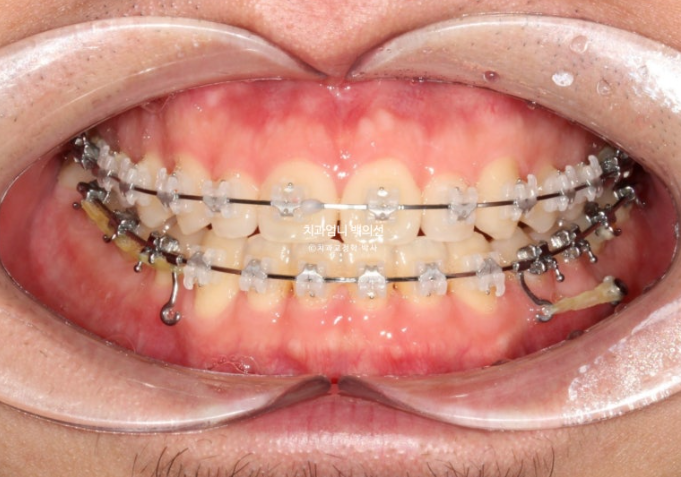

치료 시작 10개월차 모습입니다. 교정용 나사인 미니스크류를 아래쪽에 심고 사랑니 공간으로 밀어냅니다.

24.11